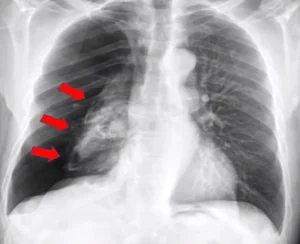

Bệnh nhiễm trùng đường hô hấp: Tổng quan về nguyên nhân, triệu chứng, cách điều trị và phòng ngừa hiệu quả để bảo vệ lá phổi của bạn

Chào bạn, hôm nay chúng ta sẽ cùng nhau tìm hiểu về một nhóm bệnh lý rất phổ biến mà hầu như ai cũng đã từng mắc phải ít nhất một lần trong